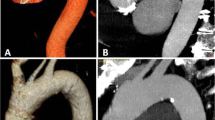

The low-tube-voltage protocol showed a 23–31 % higher mean aortic segmental attenuation (Table 5). Figure 2 shows that the attenuation profile of the low-tube-voltage protocol fluctuates at the same attenuation level, whereas the profile of the standard-tube-voltage protocol shows a drop-off at the level of the iliac arteries (ROI 6). The mean aortic attenuation gradient for the low-tube-voltage protocol was smaller than that of the standard-tube-voltage protocol (58 ± 70 HU vs. 47 ± 50 HU, respectively, P = 0.34). The proportion of aortic attenuation gradients less than 50 HU for the low-tube-voltage protocol (69 %) was slightly higher than those of the standard-tube-voltage protocol (60 %), with no significant difference (P = 0.48). Although the low-tube-voltage protocol showed a 36 % higher mean image noise (P < 0.01), the CNR values in the two protocols were similar, with no significant difference (P = 0.40–0.86).

Graph demonstrating mean aortic attenuations along the z-axis (ROI 1 = ascending aorta at the level of the main pulmonary trunk; ROI 2 = aortic arch; ROI 3 = descending aorta at the level of the main pulmonary trunk; ROI 4 = abdominal aorta at the level of the coeliac artery; ROI 5 = stent-graft main body (1 cm above bifurcation) or abdominal aorta (1 cm above bifurcation) in patients without stent placement; ROI 6 = mean of left and right external iliac arteries)